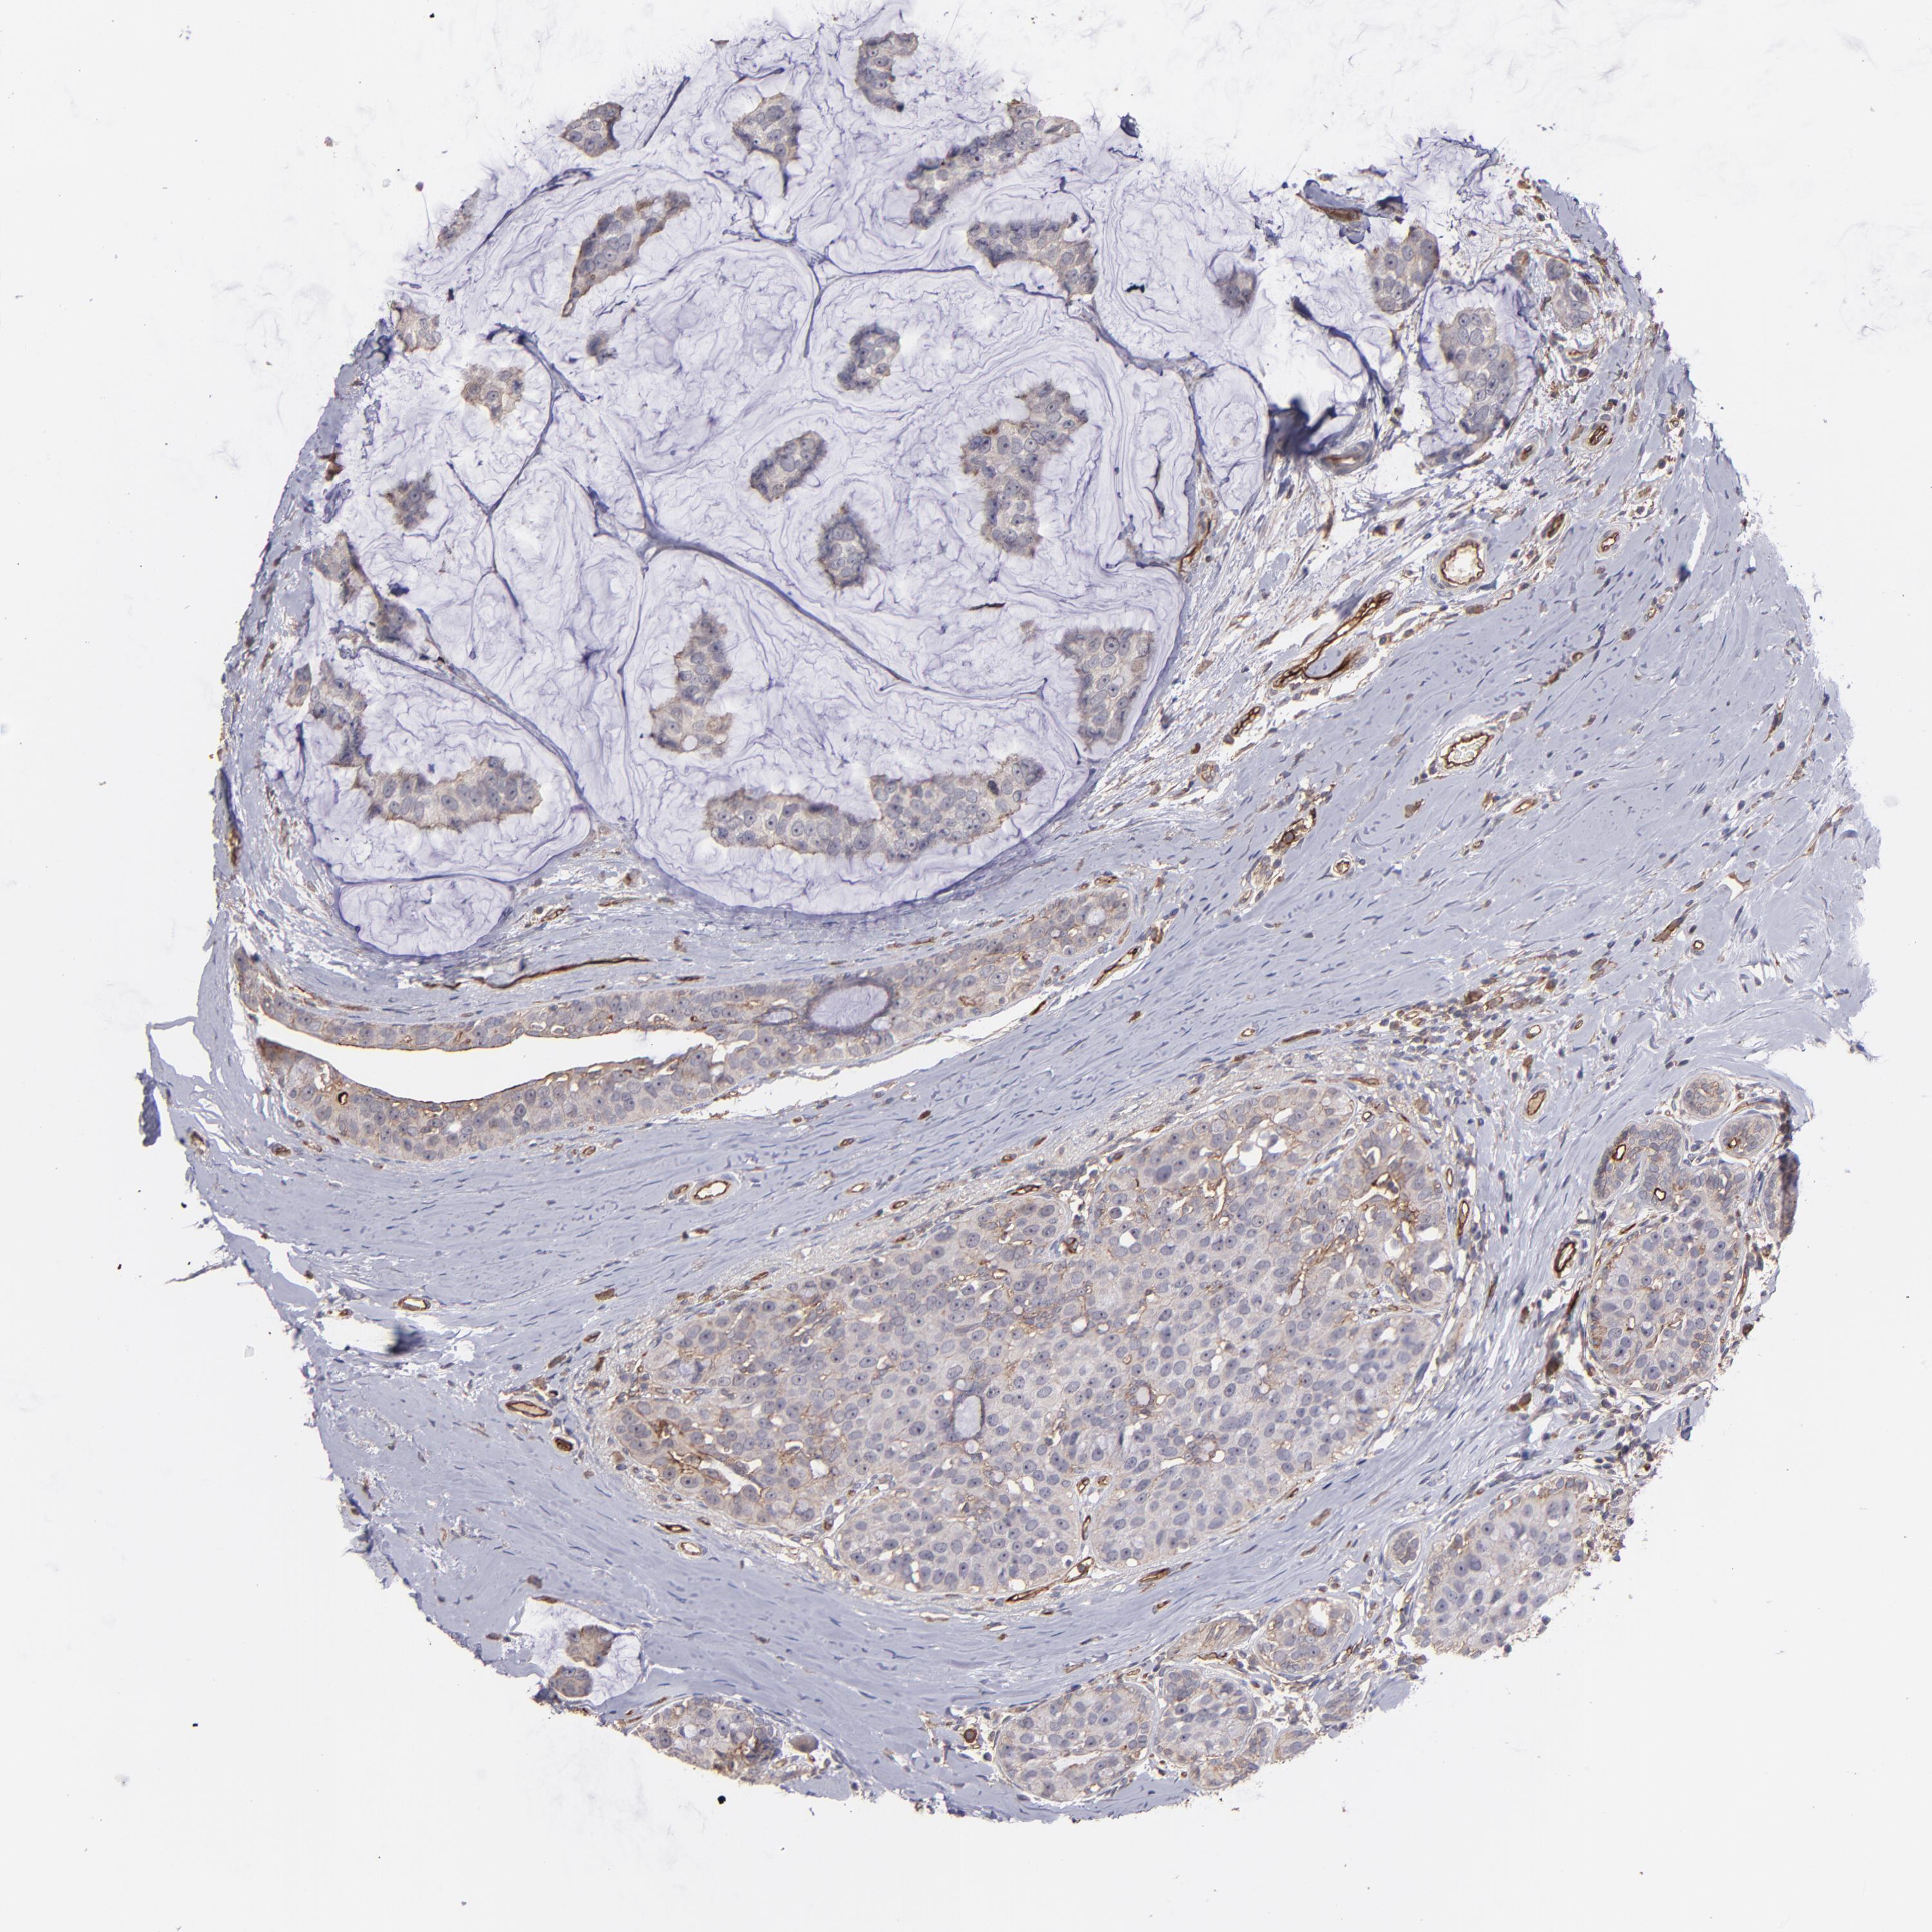

CANCER BREAST CANCER Show tissue menu

BRCA TCGA BRCA VALIDATION PROTEIN EXPRESSION